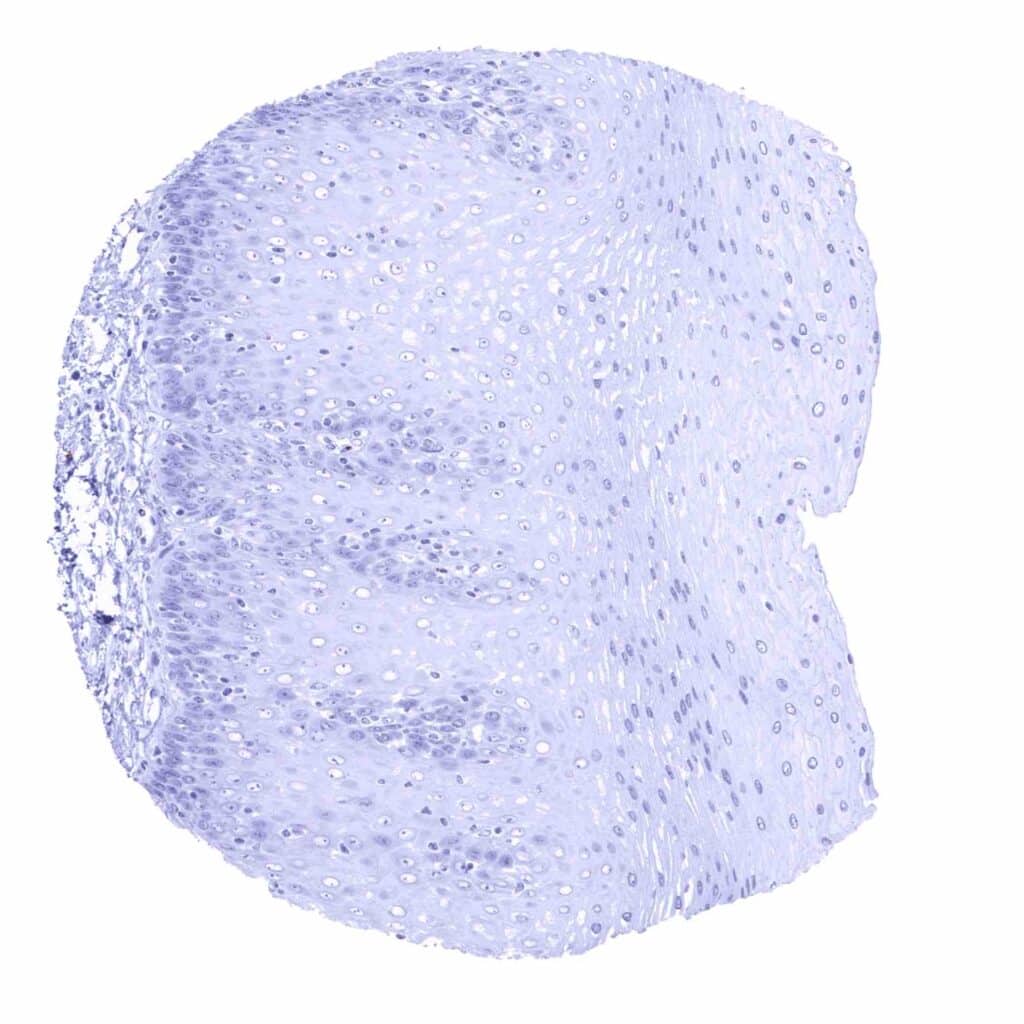

Tonsil, surface epithelium

Tonsil